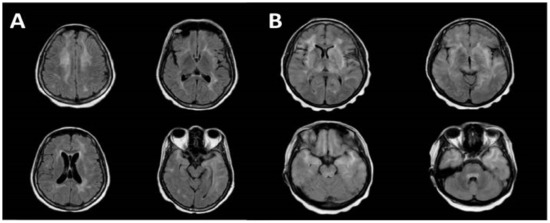

- Sakai, M.; Higashi, M.; Fujiwara, T.; Uehira, T.; Shirasaka, T.; Nakanishi, K.; Kashiwagi, N.; Tanaka, H.; Terada, H.; Tomiyama, N. MRI imaging features of HIV-related central nervous system diseases: Diagnosis by pattern recognition in daily practice. Jpn. J. Radiol. 2021, 39, 1023–1038. [Google Scholar] [CrossRef]